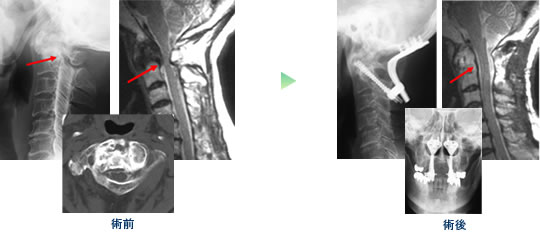

頚椎損傷 (第5頚椎tear drop骨折)

キアリ奇形+脊髄空洞症